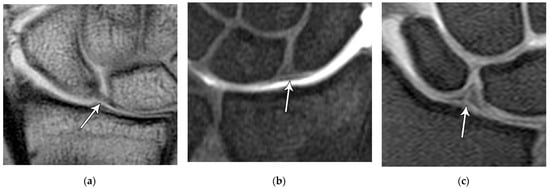

The scapholunate ligament can be thought of as having three separate components: proximal, dorsal, and volar (Figure 20) [2,14]. Tears are often traumatic in etiology (e.g., fall on outstretched hand or FOOSH) and associated with symptoms. The proximal component is also known as the “central membranous component” due to its location and composition (Figure 21a). Partial tears or degenerative perforations of this membranous portion are common and usually asymptomatic. Typically, this portion has a triangular, meniscal projection distally (Figure 21b,c). The dorsal component is the thickest and has the most significant role functionally (Figure 22). The volar component is thin and weak and, therefore, is not of great biomechanical importance, and isolated injury is uncommon.

Figure 21. (a) Coronal T1 MR image showing a normal linear morphology of the proximal scapholunate ligament (SLL). (b) In a different patient, coronal PD FS MR image showing a normal triangular morphology of the proximal SLL. (c) In a different patient, coronal PD FS MR image showing an additional normal triangular morphology of the proximal SLL with a tear.